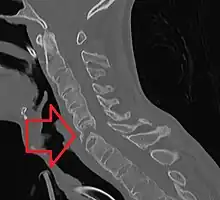

The earliest changes demonstrable by plain x–ray shows erosions and sclerosis in sacroiliac joints. Progression of the erosions leads to widening of the joint space and bony sclerosis. X-ray spine can reveal squaring of vertebrae with bony spur formation called syndesmophyte. This causes the bamboo spine appearance. A drawback of X-ray diagnosis is the signs and symptoms of AS have usually been established as long as 7–10 years prior to X-ray-evident changes occurring on a plain film X-ray, which means a delay of as long as 10 years before adequate therapies can be introduced.[19]

Lateral X-ray of the neck in ankylosing spondylitisImaging

CT scan showing bamboo spine in ankylosing spondylitis